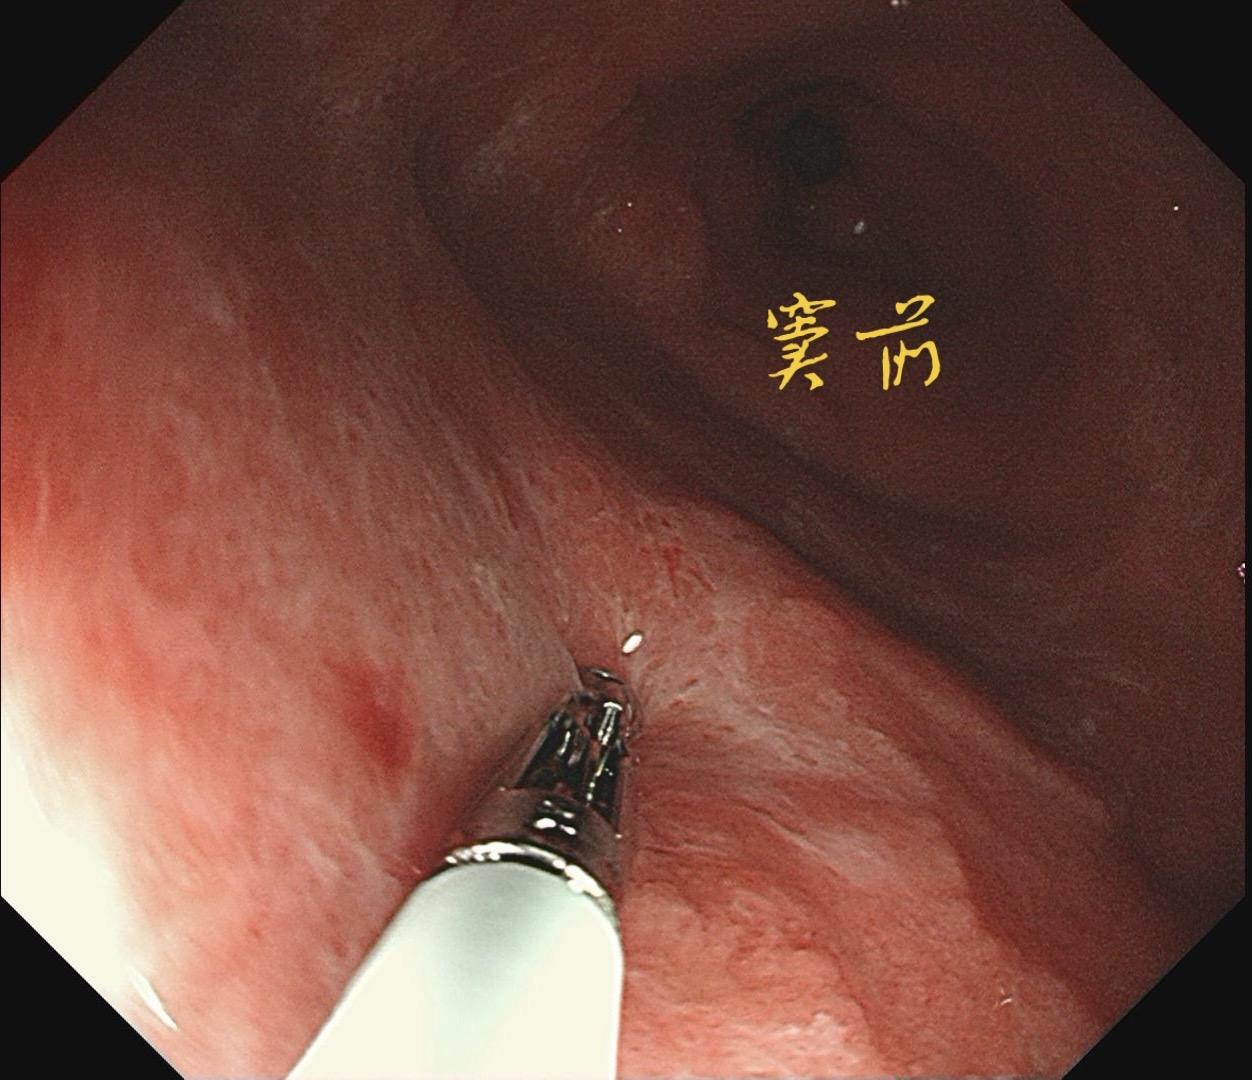

男,61岁,胃巨大褪色调病变。答案在最后一张图片,你猜对了吗? 患者因上腹部饱胀行胃镜检查,Hp阴性背景,胃窦至贲门下见一巨大褪色调病变,边界清晰,病变相对表浅,未见明显溃疡及隆起,胃壁较柔软,充气顺应性佳,予多点活检确诊,拟外科手术行全胃切除。做这么多年胃镜,还是第一次遇到这样的……